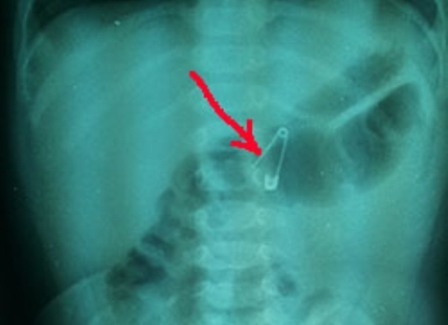

Chiếc bút chì dài khoảng 17 cm nằm trong dạ dày của Lei Bo suốt 5 năm. |

Bác sĩ điều trị cho Lei cho biết, chiếc bút chì dài khoảng 17 cm và bị ăn mòn bởi axit trong dạ dày. Chì cũng tan vào hang vị dạ dày và tá tràng.